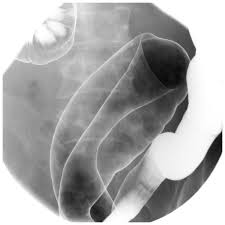

and rectum, which make up the large bowel or intestine. Inflammation is the body’s reaction to

injury or irritation and can also cause redness, swelling and pain. Tiny open sores, or ulcers,

develop on the surface of the lining, which may bleed and produce pus. When the lining

becomes inflamed it produces extra mucus.

Inflammation usually begins in the rectum and lower colon, but it may affect the entire colon. If

UC only affects the rectum, it is called proctitis.